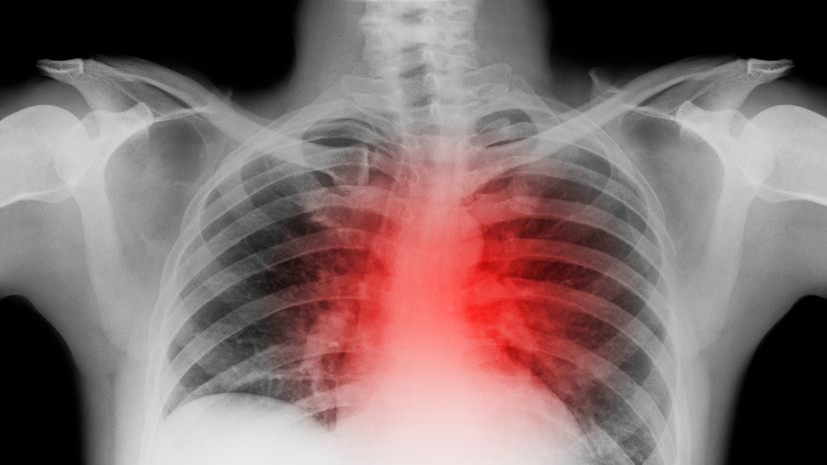

Həkim qeyd edib ki, ürək damarlarında qan dövranının zəifləməsi ciddi fəsadlara yol aça bilər. Xüsusilə ürək-damar sistemi ilə bağlı problemləri olan şəxslər üçün bu vəziyyət daha təhlükəlidir. Mütəxəssisin sözlərinə görə, bol qida qəbulundan sonra ürək daha çox yüklənir və bu da infarkt riskini artıra bilər. Bu səbəbdən yemək porsiyalarına nəzarət etmək vacibdir.